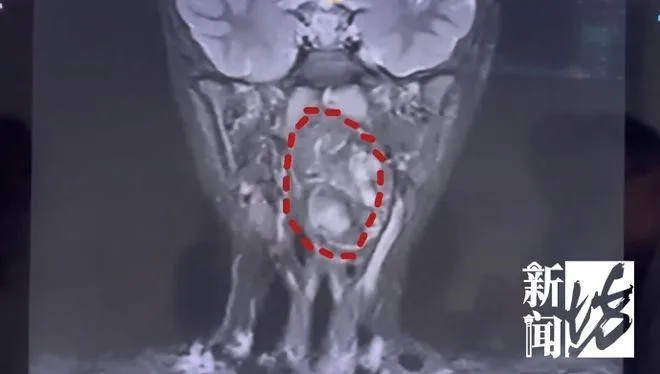

腫瘤

畸胎瘤